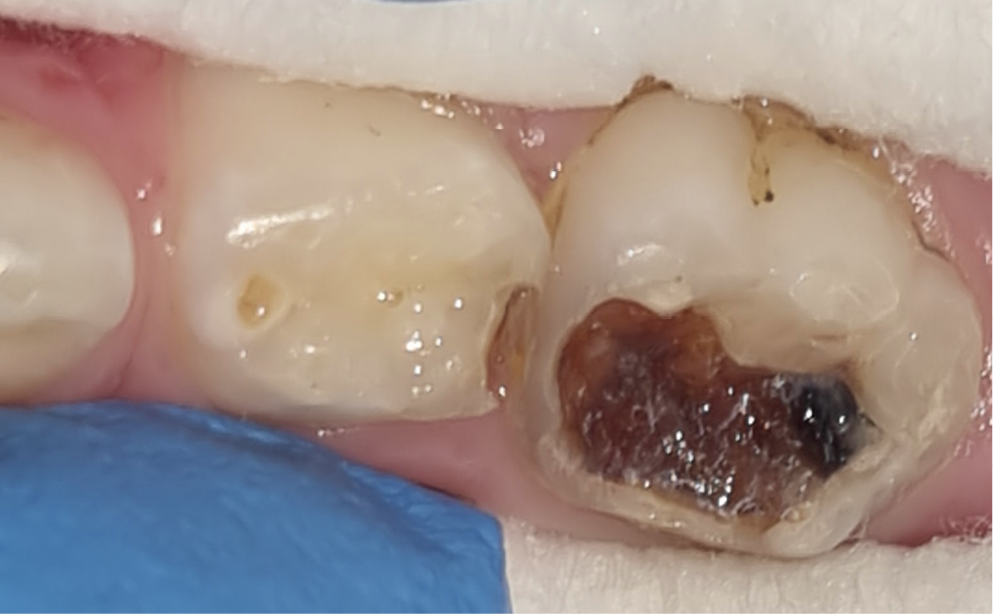

In the e-SDF® group, patients’ faces and gums were protected with a petroleum gel (Vaseline®) to avoid staining. The application of 38% SDF was performed twice with a microbrush on the affected tooth surface, and surplus material was removed using cotton pellets (Figure 4). In accordance with the manufacturer’s instructions, the time required for the material to act is 2 min per single application. The black discoloration manifested subsequent to double application of the agent (Figure 5), after which the stopwatch was halted and the duration of the procedure was recorded in the case sheet, signifying the conclusion of caries treatment.